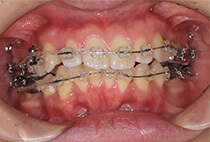

治療前